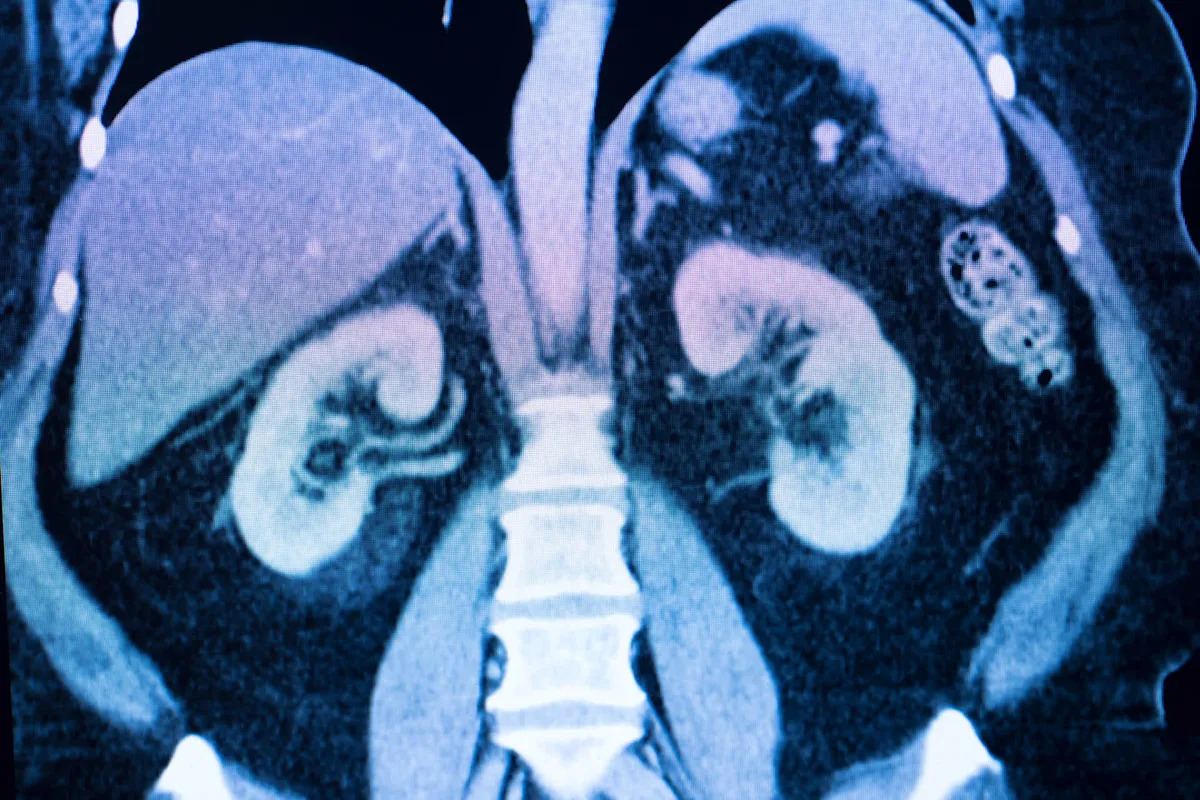

As more plastic waste is being released into the environment, microplastics in drinking water and food are being ingested by humans, causing damage to internal organs after being absorbed through the digestive system. That's most notably occurring in the kidneys, as found in a study published by Communications Biology. The study has found that microplastics — tiny plastic particles less than 5 millimeters in length — are the primary carriers of the environmental pollutant Benzo[a]pyrene into the body. The specific pathways are not fully understood, but there is evidence that BaP is being absorbed primarily through the intestines after oral ingestion, posing health risks. The peer-reviewed study found that bottled water is the main source of microplastics, doing damage to the intestinal wall and kidneys and causing systemic inflammation. Microplastics in the environment are causing a big problem since they are nearly impossible to clean up because of their tiny size. They have been found in the stomachs of humans and animals, as well as in the air, soil, tap water, food, and drinks. They are also accumulating in our oceans, causing damage to coral reefs and oceanic ecosystems. The effects of microplastics are still being studied, so we don't yet know the full extent of the potential risks to the environment or human health. Since microplastics are not found in nature and are manufactured by humans, they cannot be broken down by organisms. In a statement to The Cool Down, a representative for the International Bottled Water Association disputed the study's findings: "Very importantly, this article is based on a study stating that polystyrene microplastic particles are carriers of Benzo[a]pyrene (BAP) into living organisms," they wrote. "However, bottled water containers are not made using polystyrene. "In addition, FDA has a Standard of Quality (SOQ) for BAP of 0.2 ug/L in bottled water. The concentration of BAP used in the study was 4 ug/L, which is 20 times more than the FDA limit for bottled water. There is also an EPA MCL [maximum contaminant level] of 0.2 ug/l for tap water." The spokesperson also said that "with the high rates of obesity, diabetes, and heart disease in our on-the-go society, bottled water provides a safe, healthy, and convenient beverage choice" and that "discouraging people from choosing this healthy drink option is not in the public interest." That said, while the IBWA's concerns with the study's methodology bear mentioning, plastic bottles of soda or other drinks are equally likely to cause microplastic exposure as water bottles. This is especially concerning when and if the bottle gets hot, such as when left in a hot car, as the Today Show covered. Plastic bottles of all kinds also equally contribute to global pollution problems, as plastic can generally only be recycled one or two times before it degrades too much, while aluminum and glass are infinitely recyclable. Glass is generally the safest choice for avoiding contamination, as it is highly inert, and many aluminum bottles and cans are lined with plastic of some kind, even if they would still feature much less plastic than plastic bottles. Of course, better than all of the above is using a reusable water bottle. By reducing plastic use and recycling properly, we can reduce the amount of microplastics being released into the environment. Investing in a reusable water bottle rather than purchasing single-use plastics and using reusable containers rather than disposable bags is a simple way to reduce your use of plastics that break down into microplastics. You can also ditch plastic grocery bags and instead use reusable bags when you shop. You can also support brands that use plastic-free packaging. Do you worry about the quality of the air inside your home? Yes — often Yes — but only sometimes Only when it's bad outside No — I never do Click your choice to see results and speak your mind. Properly recycling plastics is also critical to keeping them out of the environment, where they can be broken down into microplastics that we can breathe and ingest. Scientists are working on solutions to the problem of microplastics in the environment. A filter called bioCap seems to offer promising results and is in development. Though we don't yet know the full ramifications of microplastics in the environment, by taking small steps as individuals, we can help reduce the risk. Join our free newsletter for weekly updates on the latest innovations improving our lives and shaping our future, and don't miss this cool list of easy ways to help yourself while helping the planet.